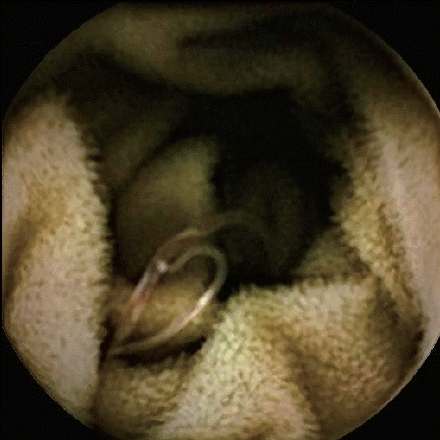

Fig. 2). A capsule endoscopy demonstrated fresh blood in the jejunum and multiple worm-like objects in the jejunum and ileum, all with a similar curvature and large “heads” (

Figs. 3,

4). The images were concerning for a hookworm infection.

Fig. 3Capsule endoscopy identified hookworms in the patient’s intestine.

Fig. 4Another capsule endoscopy identified a hookworm (arrow) in the patient’s intestine.